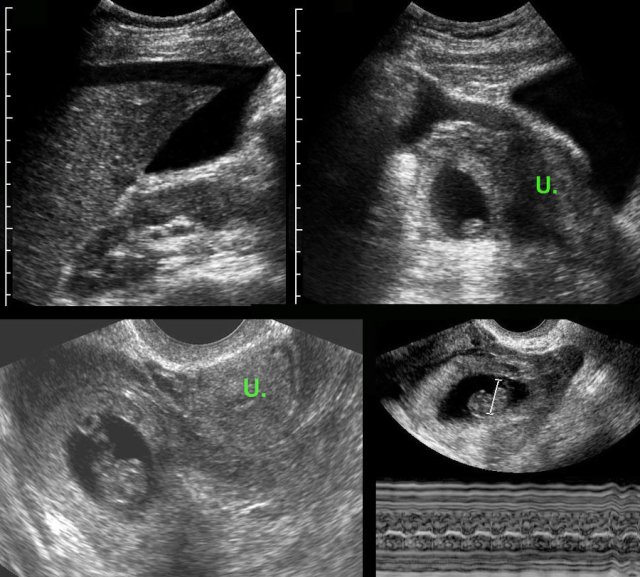

case 3

This patient was submitted for suspected perforated appendicitis.

US showed free fluid and to the right of the uterus (U.), a gestational sac containing a living fetus.

Fetal heartbeat was documented by TVUS with M-mode (right lower image).

A living fetus is found in less than 10 % of all ectopic pregnancies.